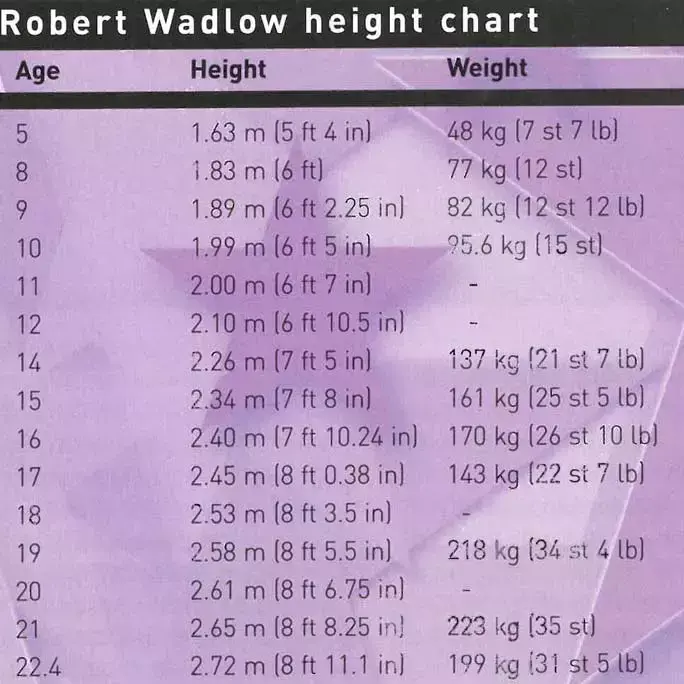

罗伯特的生长记录表

在这个之后,每量一次身高,他就刷新一次世界纪录。

到18岁,他已经拥有2.53米的身高,218公斤的体重了。

19岁时,他就凭着2.62米的身高,打破了吉尼斯纪录成为世上最高的人。

到10岁时,他的身高就达到了1.95米,体重达95公斤。

那时12岁的罗伯特,已经是个2.11米的巨人了。

即使在他死亡前一刻,他的身体可能还在继续长高 。

而在他临死之前,医院最后还给他量了一次身高。

2.72米*,“世界上最高的人”已经定格为这么个没有温度的数字。

即便已经过去78年,这个“世界最高”的吉尼斯纪录依然没有人能打破。

*注:死后躺着测试的身高为2.74米,测身高时躺着测会比站着测高一些。